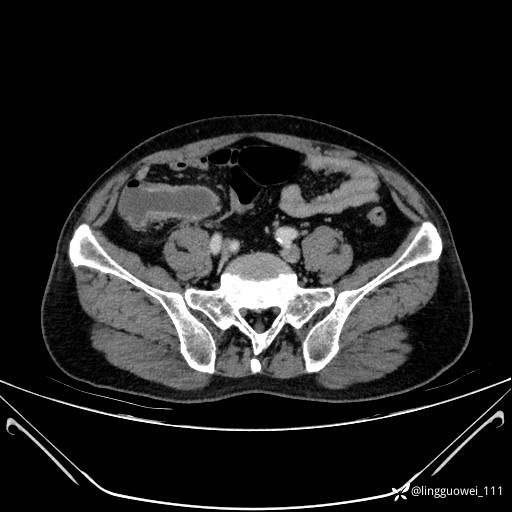

62岁,男,2天前无明显诱因出现下腹部疼痛不适,呈持续性,程度稍剧,同时伴有尿频、尿急及尿不尽感,无畏寒、发热。

平扫: